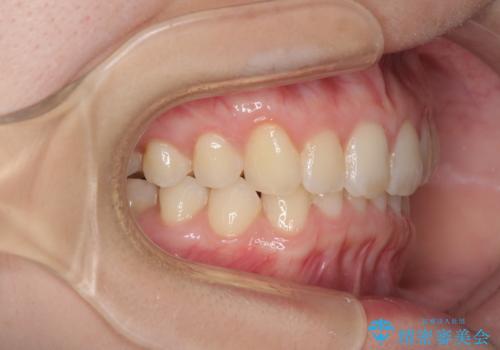

- 口元の深い咬み合わせ(ディープバイト)を気にして来院された患者様です。

インビザラインによる上下歯列の遠心移動(後方移動)により、口元のデコボコとディープバイトを改善することとしました。

下顎左右の犬歯とその後ろにある第一小臼歯、計4歯がシミュレーション通りに動かずディープバイトがなかなか改善されませんでした。

マウスピースの再製作を何度か行いましたがうまくいかないため、部分的にワイヤー矯正を併用することを提案しました。しかし、最も気になっていた前歯のデコボコはきれいに改善されたため、これ以上治療を希望されず、治療を終了することとしました。(今後気になった際には再開する予定です)